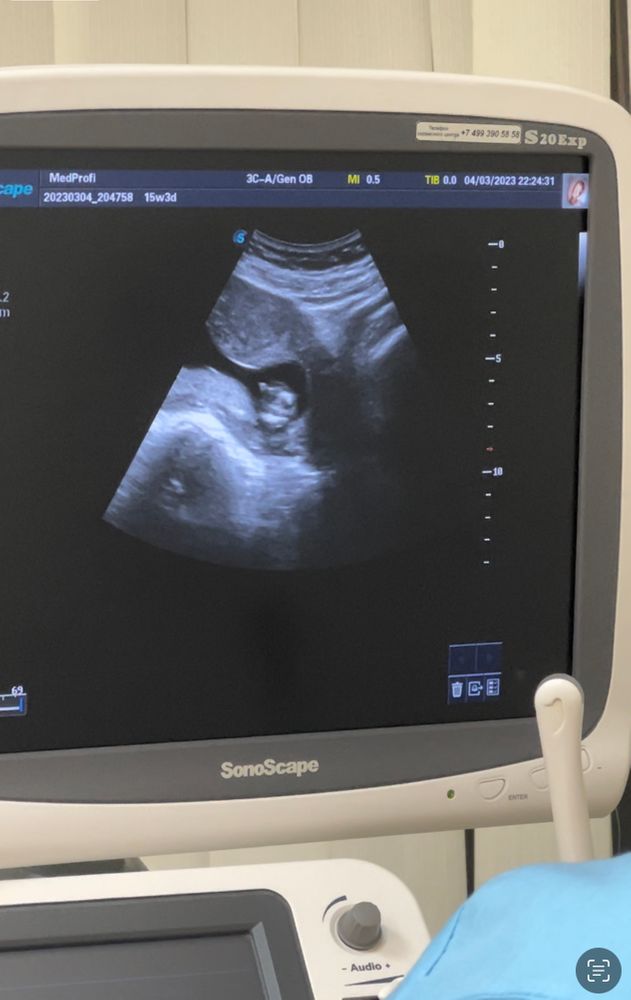

Пол ребёнка

Похоже на девочку)

Видно плохо, но на втором фото вполне может быть девочка, вроде бы видно "кофейное зёрнышко". Но, повторюсь - на этих снимках видно плохо.

Сегодня сказали,что будет мальчик. Закрашиваю кружок ☺️